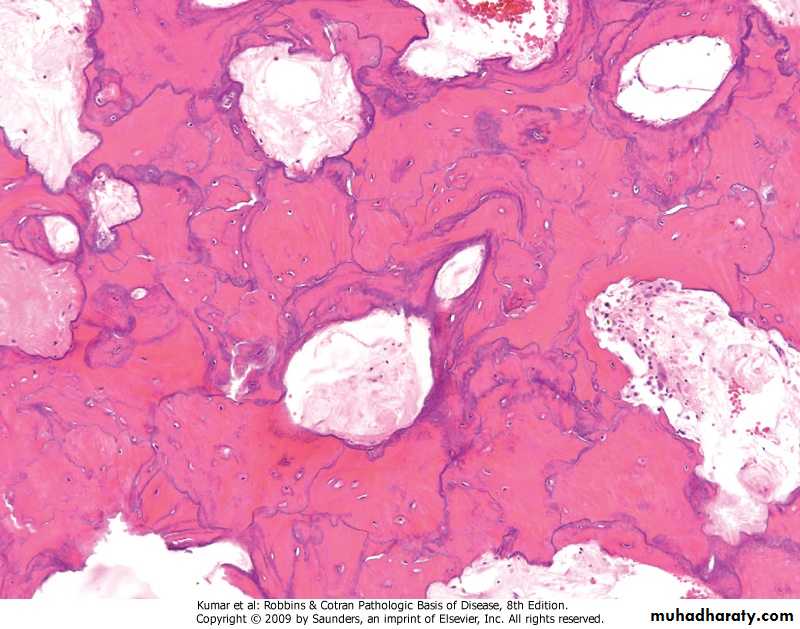

FD showing irregular trabecullae (C-shaped or Chinese characters shaped trabaculae, (described as "Chinese letters“) which are usually coarse woven bone, are seen instead of well-organized lamellar bone. with compact stroma of interlacing collagen fibers

FD. Composed of curvilinear trabeculae of woven bone that lack conspicuous osteoblastic rimming and arise in a background of fibrous tissue.